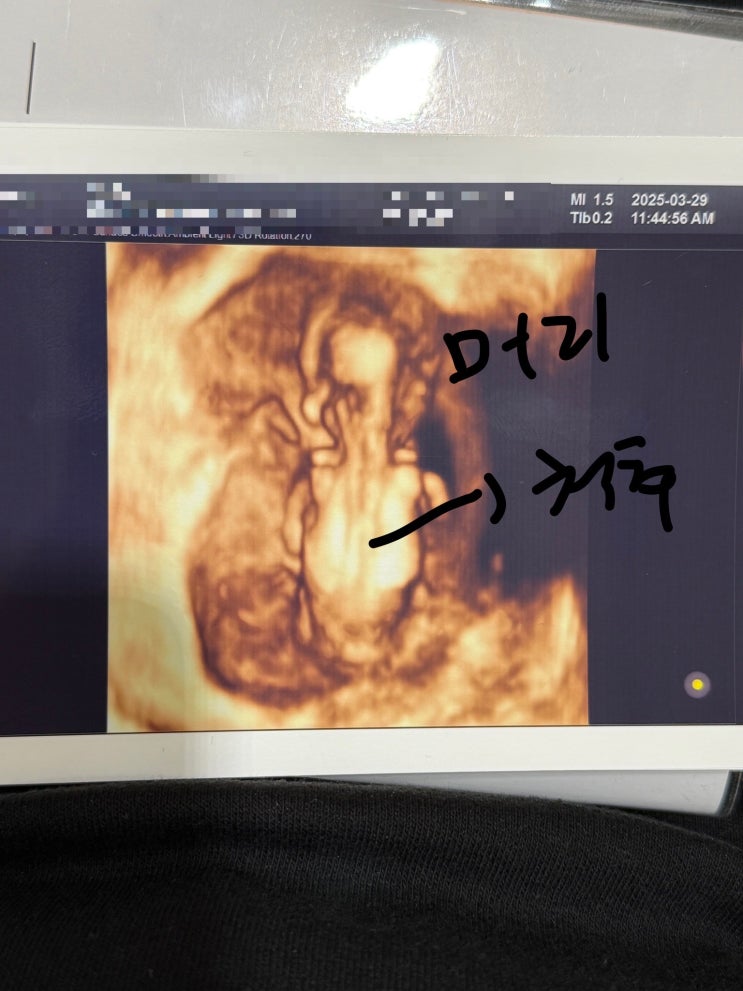

임신 12주차 입체초음파 후기

임신 12주차 입체초음파 후기 유난대디가 엄마 대신에 적는 태아 블로그 ~ 12주차 3일 ~ 입체 초음파와 니...